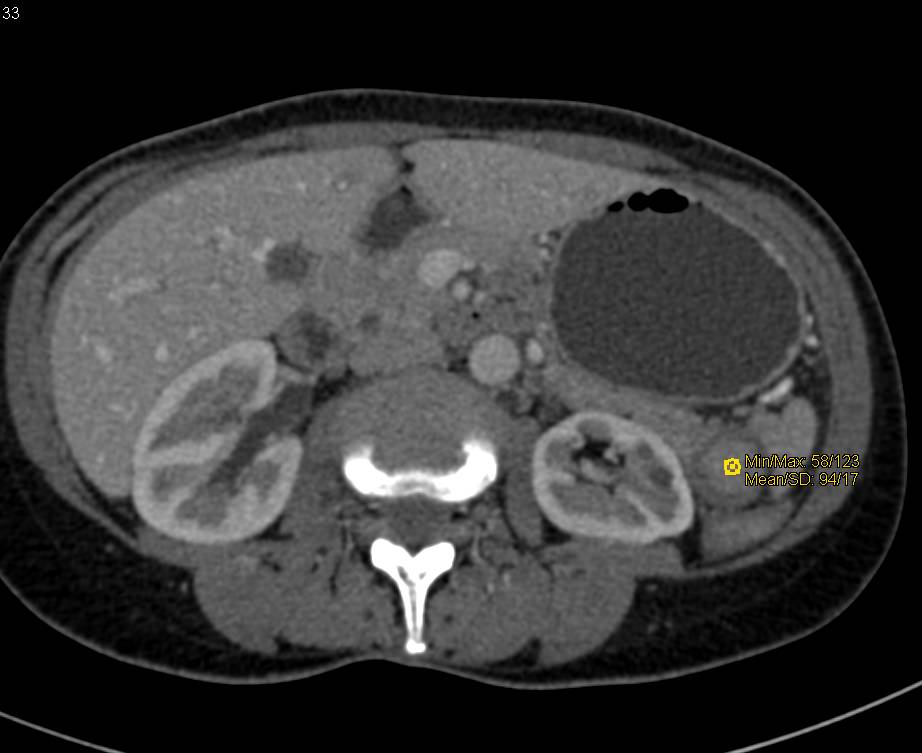

Granulomatous Disease in Spleen